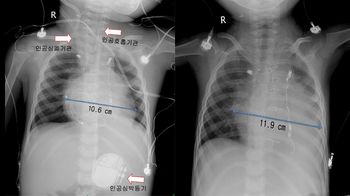

°Ç´ë, ¸ö¹«°Ô 40kg ±Øº¹ ½ÉÀåÀÌ½Ä ¼º°ø

°Ç±¹´ëº´¿ø ¼Ò¾Æ½ÉÀå¿Ü°ú ¼­µ¿¸¸ ±³¼öÆÀÀÌ ÃÖ±Ù ¸ö¹«°Ô 12kgÀÇ 3¼¼ ȯ¾Æ¿¡°Ô üÁß 52kgÀÎ 27¼¼ ¼ºÀÎ ³ú»çÀÚÀÇ ½ÉÀåÀ» À̽ÄÇÏ2012-07-27 06:46:32